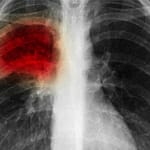

Tıp dünyasında yeni bir gelişme yaşandı. Amerikalı bir firma, akciğer biyopsisini kolaylaştırarak, tanıyı hızlandıran robotik bir cihaz geliştirdi. Uzmanlar, bu robotik sistemin akciğer cerrahisi ve tedavisinin geleceğinde çok önemli bir role sahip olacağını söylüyor.